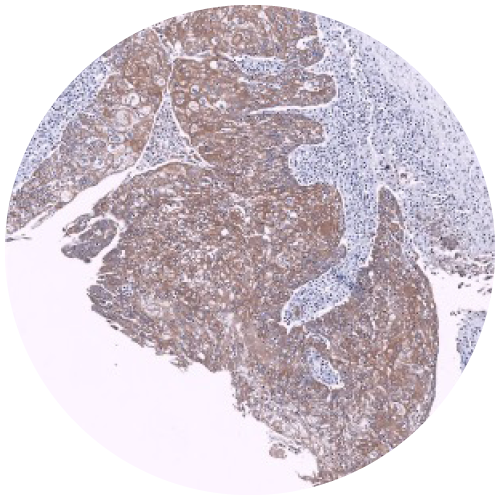

Physical IHC

Virtual IHC

Advantages of Virtual Staining

Easily integrated into preclinical & clinical workflows

Eliminates time and cost constraints associated with traditional IHC and IF

Multiplexing allows for greater biomarker characterization

Preserves scarce tissue samples

Consistent and reproducible immunostaining, every time

May be trained to any biomarker across any disease type and species